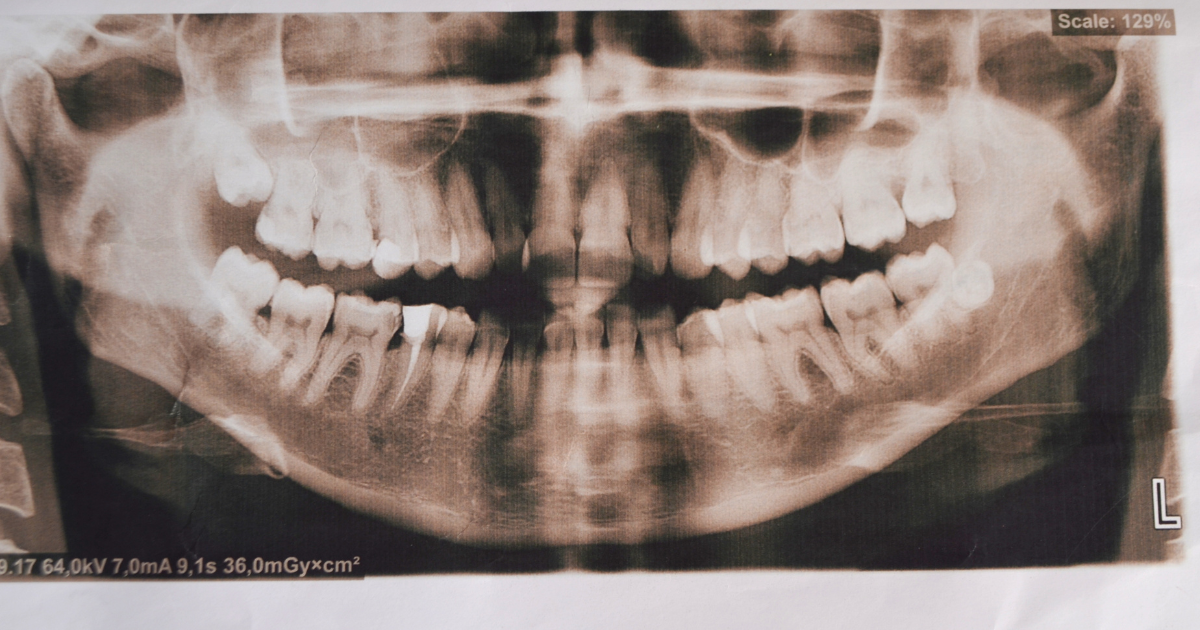

Even in more extreme cases, the patient might not know there is a problem because their extra teeth have not yet fully emerged. That was the case with a 2011 medical incident where a young lady who was 11 years old went to the dentist. When the dentist took some X-rays, they discovered that she had 81 teeth. That included all but two of her baby teeth, all of her normal adult teeth, and nearly an entire set of additional adult teeth.

Shutterstock

Most of these teeth had not yet emerged, so the patient and her family didn’t notice. In most cases like this, the extra teeth will be surgically removed so that they do not cause problems down the road. Usually, orthodontics will also be necessary to ensure that the teeth she can keep will be positioned properly.